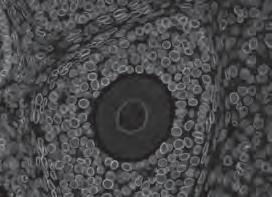

That total was enough for Hudson Institute to purchase a digital microscope with computer software that allows us to recognise and analyse cancer cells grown from patients.

The microscope, with a plaque in Jessica’s memory, was unveiled in late 2022 in the Centre for Cancer Research in a touching ceremony attended by the Lindner family.